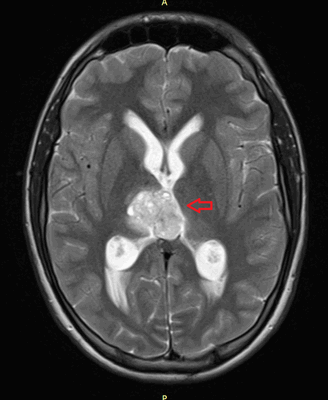

Герминомы формируют инфильтрирующие опухоли больших размеров, часто являющиеся источниками субарахноидальных (между мягкой и паутинной оболочками мозга) и вентрикулярных (желудочковых) метастаз.

Рисунок 7. - Герминома головного мозга.

Рисунок 9. - метастаз в головной мозг при герминогенной опухоли.

Лечение

Также выполняют МРТ головного мозга, чтобы выявить наличие метастазов в нем.

![Метастаз в головной мозг при герминогенных опухолях (МРТ головного мозга)]()

Метастаз в головной мозг при герминогенных опухолях (МРТ головного мозга)